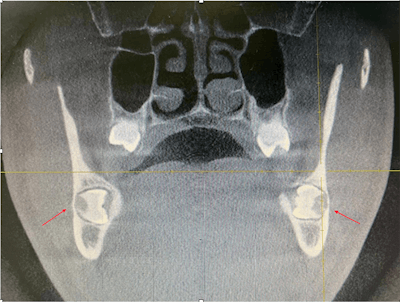

In the case report, the authors described how during the man's routine dental visit, bilateral impacted mandibular third molars were identified on a panoramic dental x-ray. The molars were transverse in the linguobuccal direction. A cone-beam computed tomography (CBCT) scan confirmed the molars were positioned in a linguobuccal direction on both sides, with thinning on the lingual cortical plates. No pathological findings were associated with the molars, the authors wrote.

Detailed evaluation of the CBCT results indicated the roots of the impacted teeth were not completely formed, and there was idiopathic osteosclerosis in the second premolar region, they wrote.